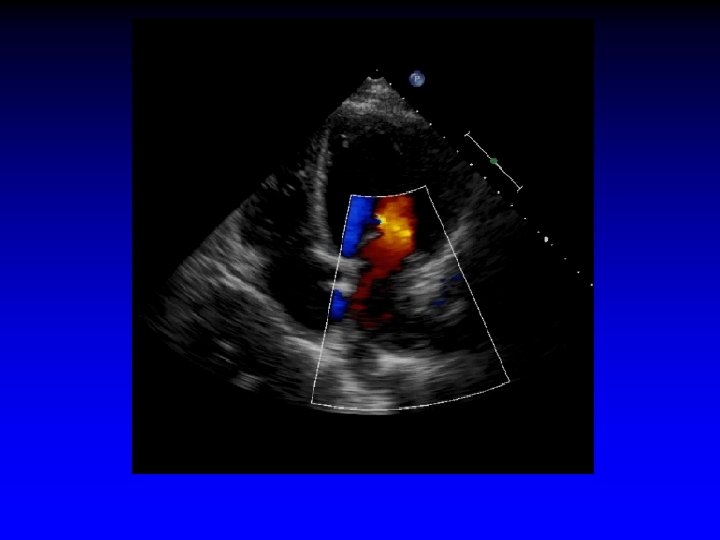

Case 7 Ischemic MR restricted PML

LVIDd = 6. 4 cm Dilated LV; posterior wall thinner than septum